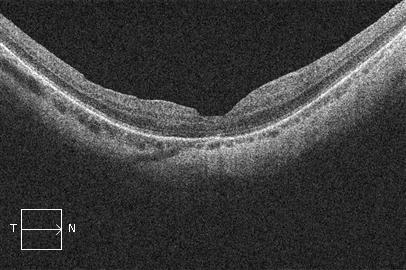

El agujero macular se diagnostica mediante un examen del fondo del ojo y la realización de una OCT.

OCT - Agujero macular